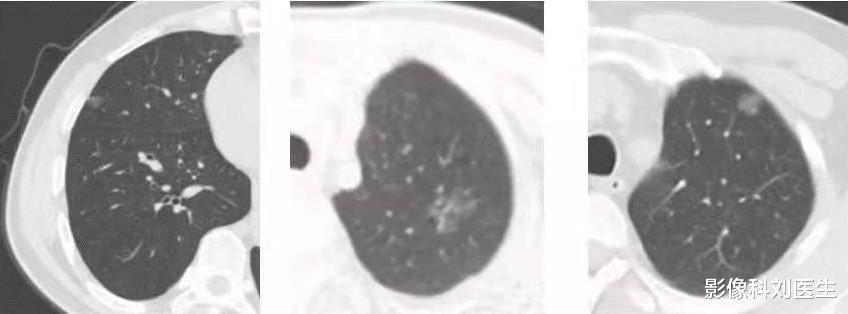

对于已经有肺结节的人群 , 需要根据结节选择多久做一次CT而如果在体检过程中发现了肺结节 , 那么这个时候对于CT检查的时间 , 是需要根据肺结节的大小、成分、形态而定的 。 在这里刘医生给大家列举一下随访时间的选择:

对于小于5mm的实性肺结节 , 刘医生建议可以每年定期复查一次即可;而对于5—8mm的实性结节 , 可以6—12个月复查一次;而对于大于8mm的实性结节 , 建议3个月复查一次 , 如果没有变化 , 可以间隔半年复查 , 2年后可以转为每年复查一次 。 而如果随访过程中逐渐增大 , 那么一定要及时进行治疗 。

而对于磨玻璃结节和混合密度结节 , 如果小于5mm , 可以在6个月、12个月、24个月时分别复查一次 , 如果没有变化 , 则可以改为年度随访;而如果结节在5—8mm之间 , 则可以3个月、6个月、12个月、24个月的时候分别复查一次;而如果结节大于8mm , 则需要评估结节形态 , 如果形态上有恶性征象 , 则需要立即处理;如果通过形态上没有办法确定 , 那么建议每3个月就要复查一次;总的来说 , 对于大于8mm的磨玻璃和混合密度结节 , 如果长期存在 , 其危险性是非常高的 , 所以要尽量确定其性质 , 及时治疗 。